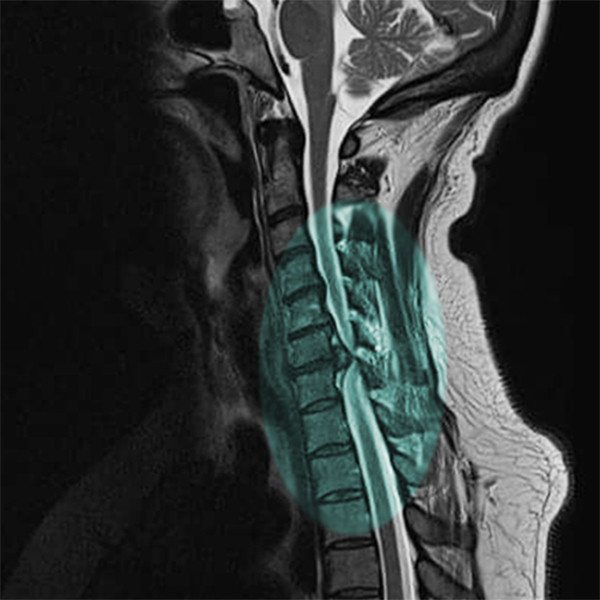

Degenerative cervical myelopathy is the number one spinal impairment in the world—affecting as many as 2 percent of adults—and an AO Spine project is bringing together research groups worldwide to accelerate research to improve DCM outcomes.